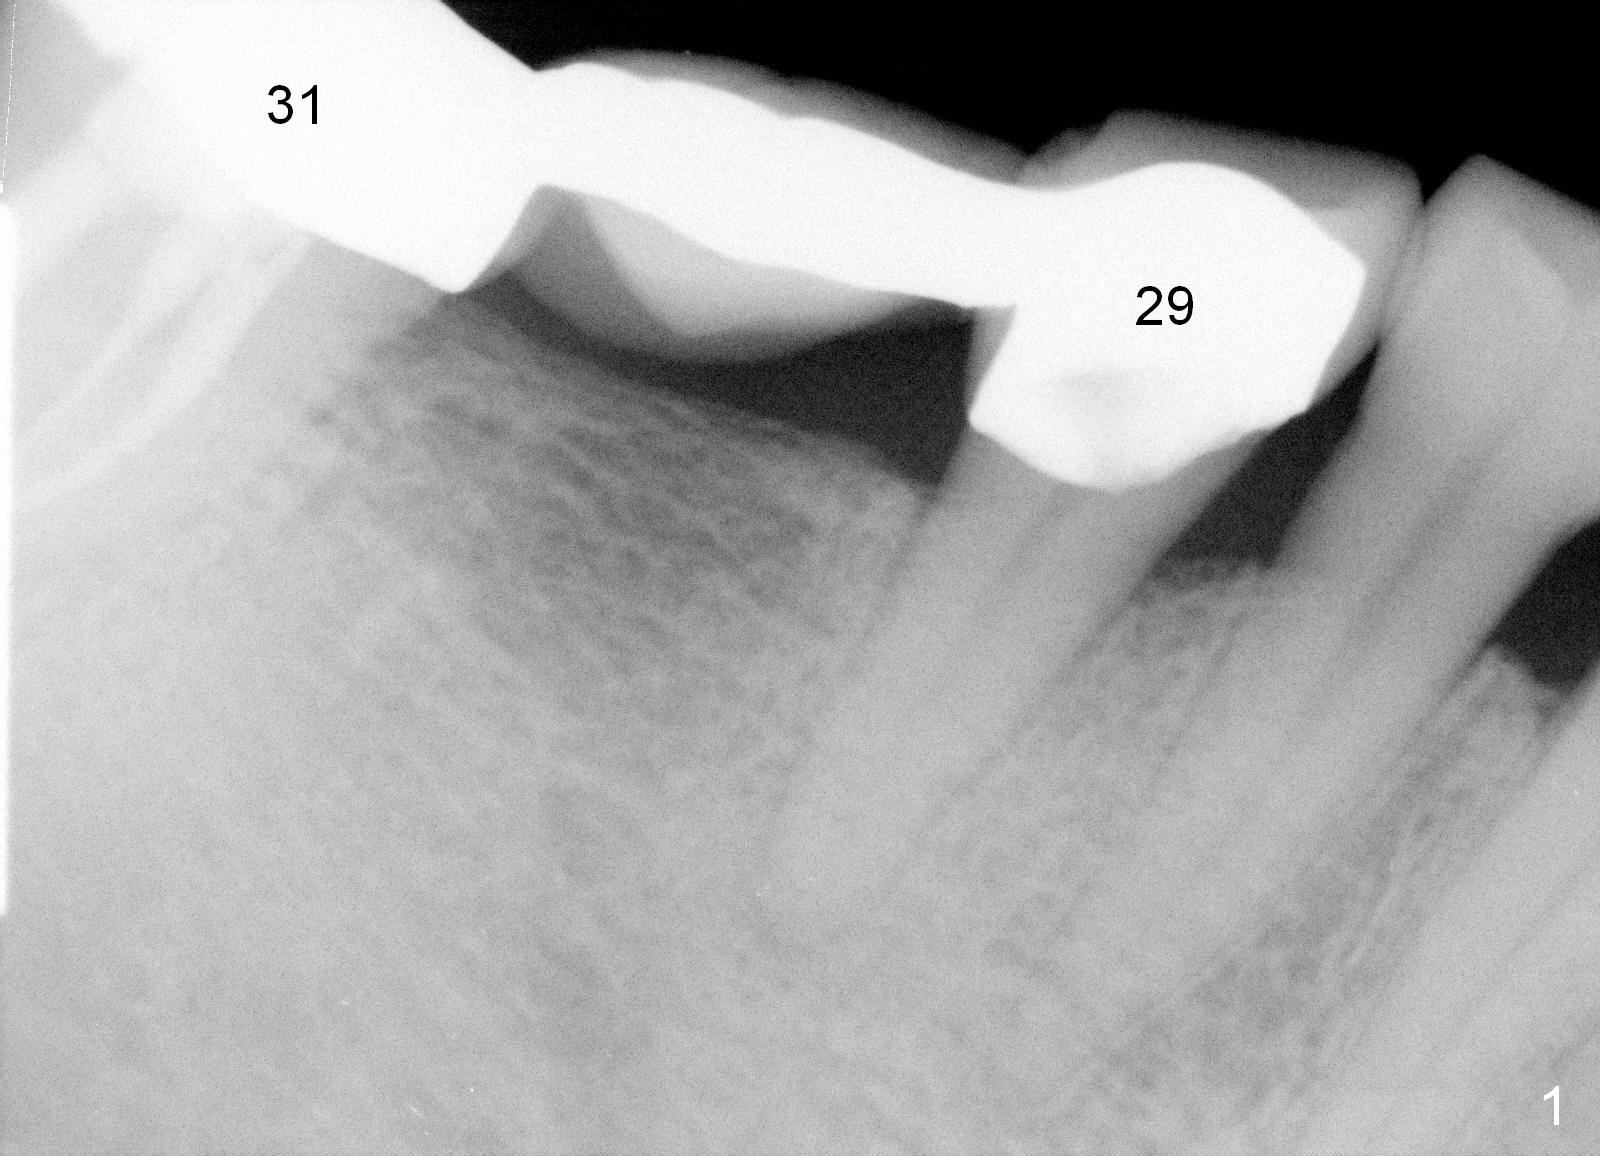

Therefore a larger and longer abutment should be used (4.5x5 mm 0°). First of all, install Isolite. Remove cement from the access hole of the unipost with Cavitron. The cement was used to cement the crown. Use Tatum driver to remove the abutment. If it does not work, make a slot on the top of the abutment and use a regular screw driver to unscrew the abutment. Second, apply Cetacaine and perform laser gingivectomy to expose the implant margin. Temporary crown should be made to keep the margin and the space just created around the implant. Third try in the new abutment. Fourth reduce the abutment height carefully and make slopes corresponding the cusps of the opposing tooth. Reduce the opposing tooth if necessary. Last, consider Ketac cementation. Use resin bonding (with syringe tip) when an angled abutment is used. The bonding has higher retention than Ketac.

Pre-impression photos show supraerupted #3 (Fig.7). Clearance is a little more than 1 mm between the mesiopalatal cusp of #3 (Fig.7 *) and the rounded abutment (Fig.8). Removal of the abutment turns out to be easy. Reduction is confined to the opposing tooth (slopes of the cusps). No occlusal reduction is done for the new abutment as mentioned above except for 2 retention grooves. One-mm reduction ring barely passes the occlusal clearance (Fig.9). No cement is applied to the abutment in case a longer abutment may be required. Bone density seems to remain the same or increase after cementation of a new crown (Fig.7). The redo crown remains in place 1 year post cementation.